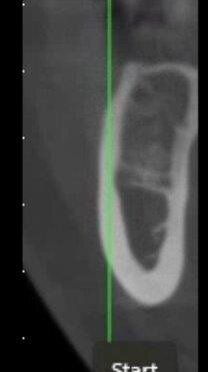

La tecnica denominata M.T.G. (Matrix Tissue Graft) si basa sull’utilizzo di una particolare matrice dermica acellulare riassorbibile di origine suina caratterizzata da un elevata consistenza e stabilità volumetrica che viene posizionata al di sotto del lembo muco periostale eseguito a spessore totale, in contatto con la cresta ossea. La stabilizzazione della matrice avviene senza mezzi di fissazione o in casi limitati mediante l’ausilio di una sutura riassorbibile con cui ancorare la matrice al lembo mucoperiosteo.

Nello studio sono stati inclusi 20 pazienti (12 donne e 8 uomini) di età compresa tra i 28 e i 65 anni, con edentulia singola e conseguente deficit vestibolare dei tessuti molli. La matrice dermica a elevata consistenza è stata opportunamente ritagliata mediante forbici e lama ed è stata posizionata al di sotto del lembo muco periostale allestito con approccio a spessore totale, vestibolarmente alla cresta ossea in cui è stato posizionato contestualmente un impianto endosseo osteointegrabile. Non si è utilizzato alcun ausilio di fissazione per la matrice dermica che è stata stabilizzata dal solo lembo di accesso ribaltato su di essa e suturato, mediante punti staccati semplici, al lembo linguale.